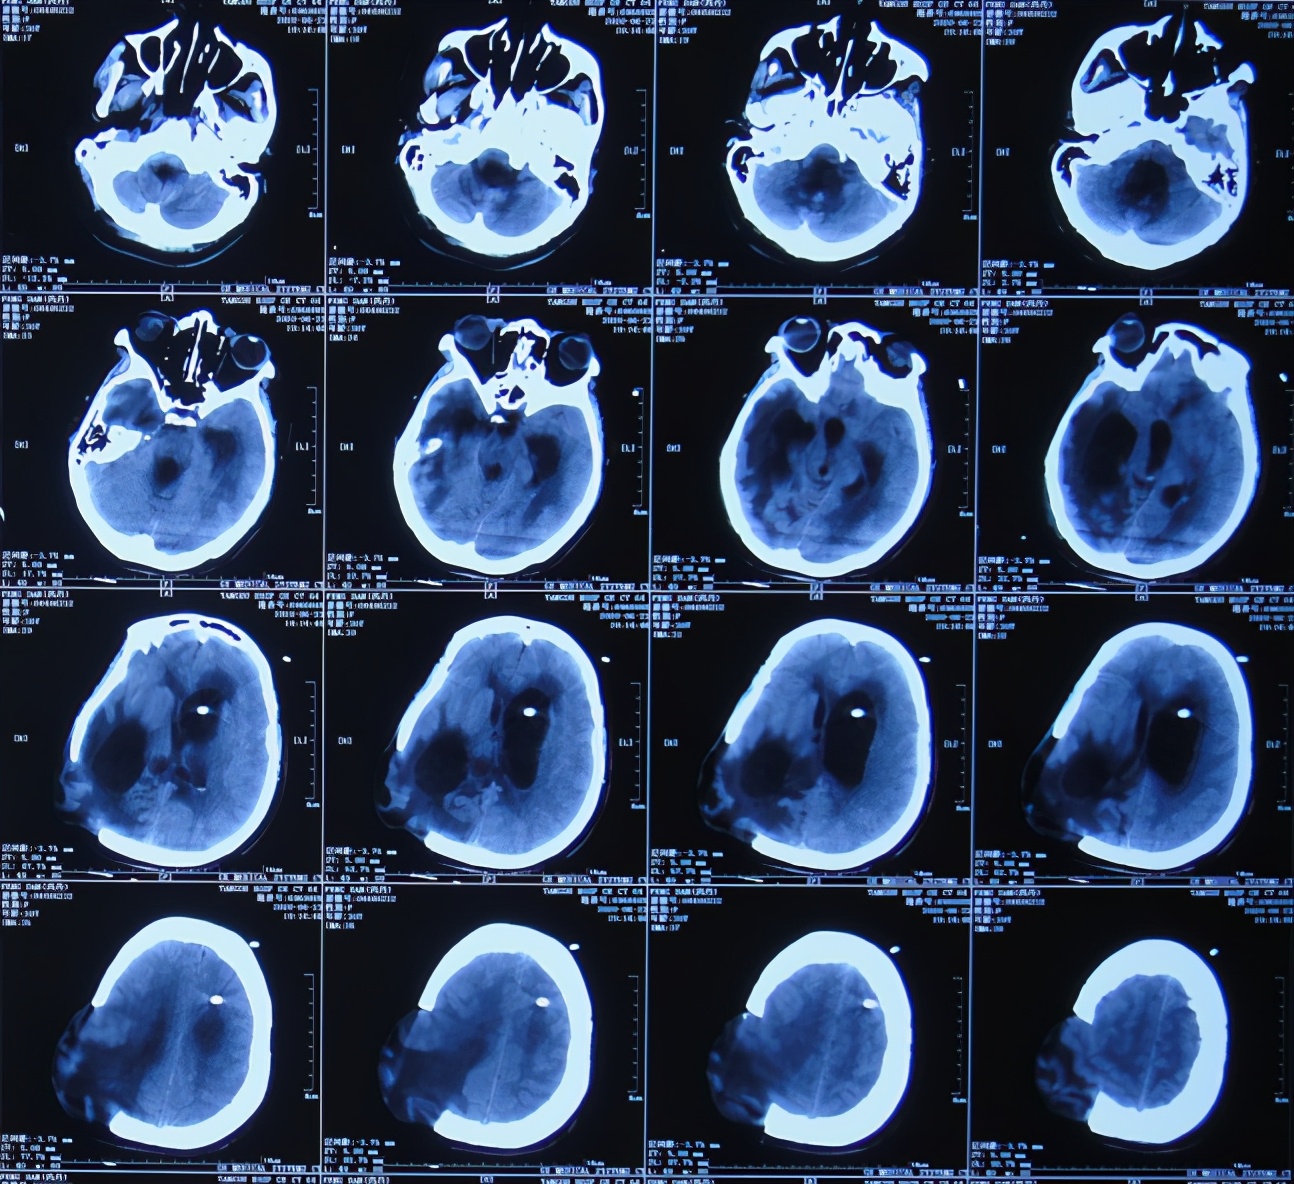

入院当天复查头颅CT示脑血管畸形术后改变,脑积水引流术后,脑膨出,右侧颞枕顶叶及左侧额叶脑水肿,严重脑室粘连( 图-17 );胸部CT示双肺肺炎(片子丢失)。

图-17: 2020年7月5日头颅CT

入院次日即2020年7月6日,进行了颞角外引流术,术后当天复查头颅CT示脑室内有2根管( 图-18 ), 脑脊液细菌培养示肺炎克雷伯菌(仍是外院开颅术后14天时查出的细菌,说明之前的细菌一直并未彻底消灭)。

图-18: 2020年7月6日头颅CT